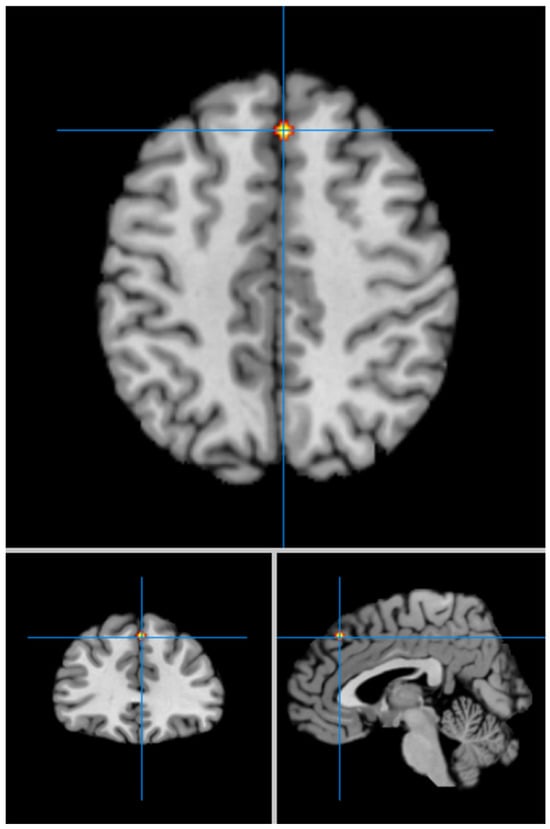

Our second analysis with cluster-level correction showed in LLD vs. HCs significant hyperfunctioning of the left superior temporal gyrus (BA 42) (MNI coordinates x = −60; y = −30; z = 14) (FWE p < 0.05) (Figure 2), and significant hypofunctioning of the right medial frontal gyrus (BA 8) (MNI coordinates x = 4; y = 32; z = 44) (Figure 3). We summarize the results of our meta-analysis in Table 2.

Figure 3.

Significant hypofunctioning of the right medial/superior frontal gyri (MNI: 4, 32, 44) in LLD (FWE corrected).

The first most important finding of our meta-analysis is the hypofunctioning of the right medial/superior frontal gyri (BA 8) in LLD compared to HCs. Traditionally known as the “frontal eye field”, BA 8 exhibits diverse functional involvement spanning motor, language, executive functions, memory, and attention [,,,,].